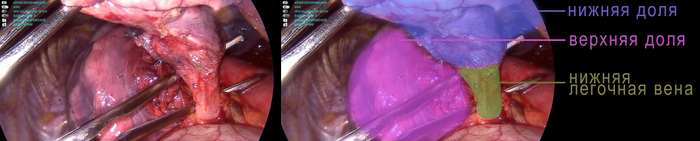

Как удалить долю? Для этого нужно знать что эту долю внутри держит. А держит ее легочная связка, нижняя легочная вена, артерия 6 сегмента, артерия базальных сегментов, бронх нижней доли и собственно самое легкое, которые связано с верхней долей. Итак, доступ сделан, камера введена, начинаем, выделять, разделять, прошивать и пересекать. Нами используется оптика увеличением, поэтому все скопления крови, которые вы увидите ниже, на самом деле гораздо меньше. Кровопотеря при таких операциях не больше 50-100 мл.

Разделив связку, мы выходим на нижнюю легочную вену, которая собирает кровь от нижней доли легкого. Разделив окружающие мягкие ткани, вена оказывается полностью на инструменте

Вена выделена, под нее заводится аппарат, вена прошивается и пересекается.

Следующий этап – выделение артерий. К нижней доле идут два артериальный сосуда – артерия 6 сегмента (А6) и артерия базальных сегментов (А8-10). Искать артерии нужно в междолевой борозде. Борозда раскрыта, сосуды найдены.

В данном случае сосуды располагались очень удачно, и нам получилось их обработать одним аппаратом. Для простоты заведения аппарата под артерии подводится резиновая держалка.